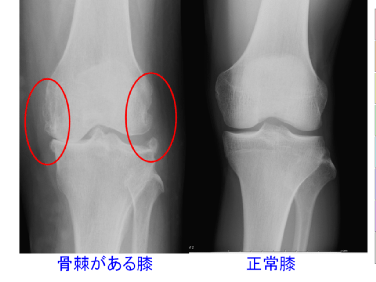

写真をご覧ください!!

膝のレントゲンですが、どちらが痛いでしょうか?

右と左のひざを比べると、左の写真のひざには変形があり、いかにも痛そうですが、実はこの方は痛みがありませんでした。